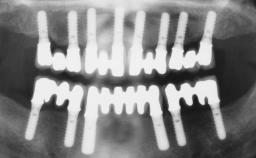

A 31-year-old man presented to our clinic 30 days after a motor vehicle accident in which he had suffered a dentoalveolar fracture in the anterior maxilla, including avulsion of teeth 12 and 11 and luxation of tooth 21. He was first treated on the night of the accident in a small city hospital with no oral and maxillofacial surgeon on the staff. A wired retention had been applied and the teeth repositioned to the best of the clinicians’ abilities. When he first presented to our care, the patient showed extrusion of teeth 12 and 11 associated with gingival recession due to bone loss in the anterior maxilla, and the stainless steel wires were still present.